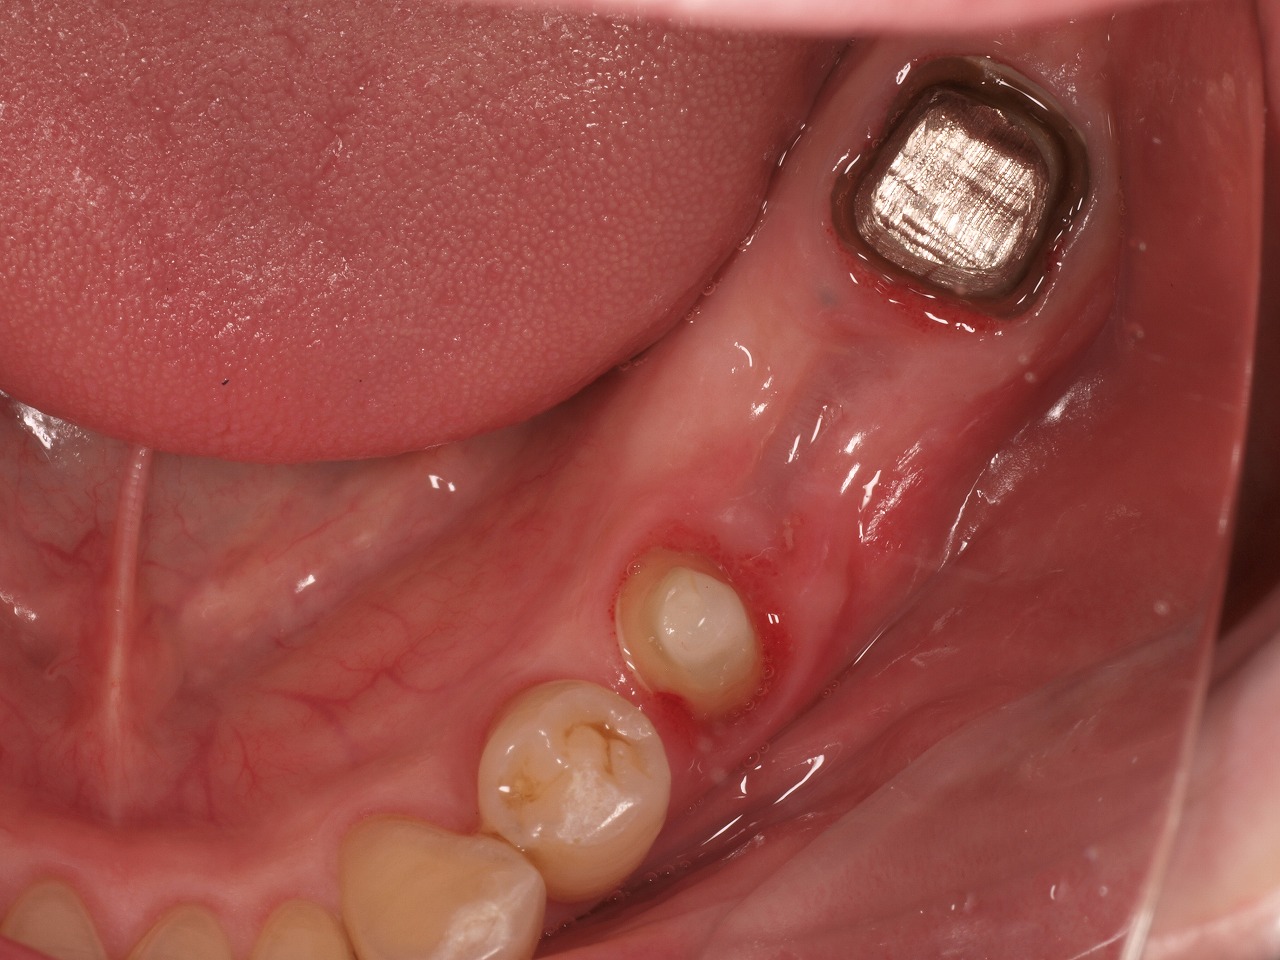

下顎の状態になります

左下は歯が割れたことにより、抜歯を行っています

クリアランスをしっかりと取っています

支台歯形成は終えています

型取りを行う前の状態になります